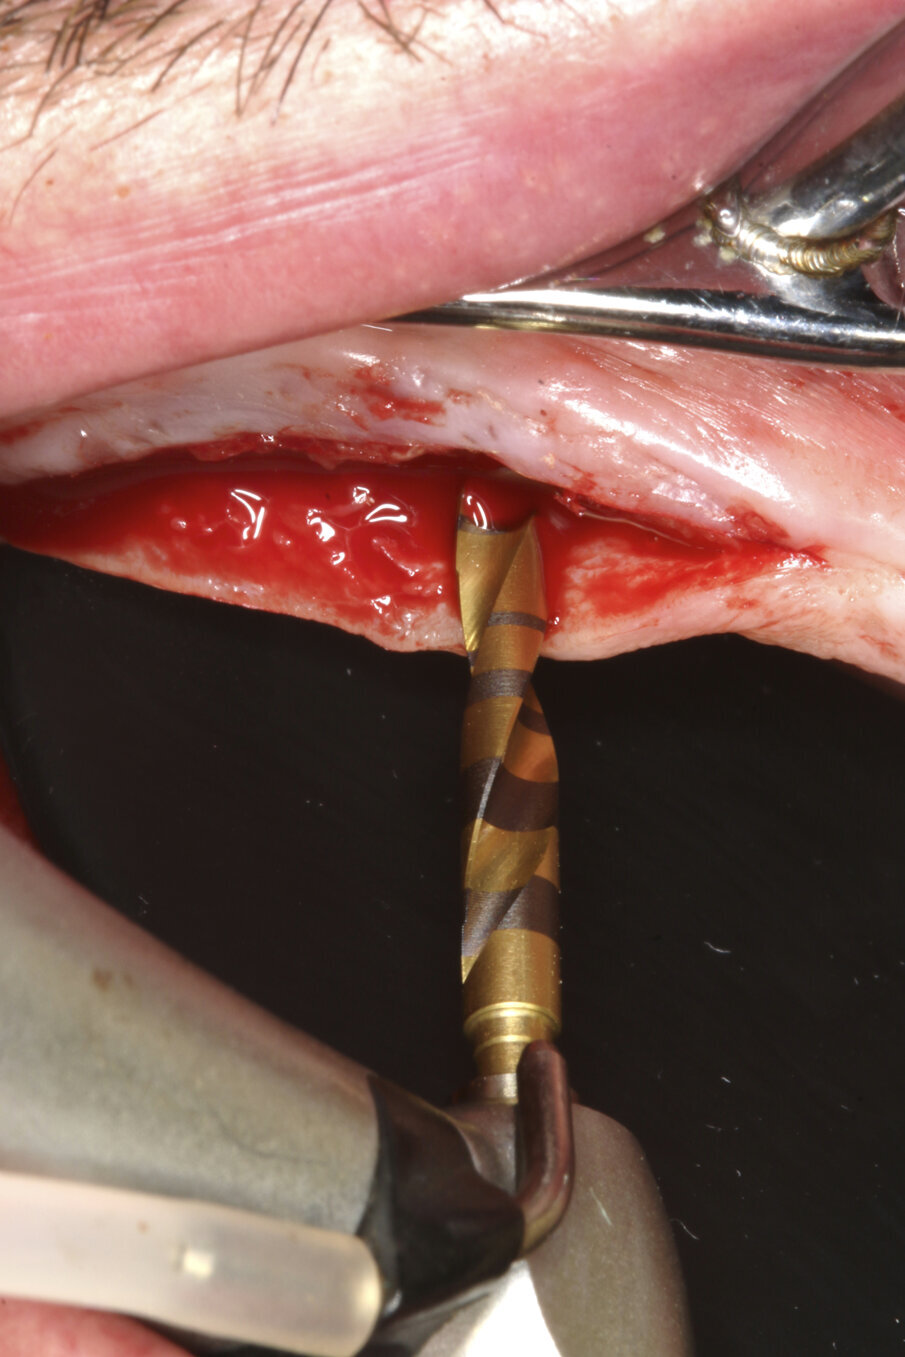

Prior to surgery, intra-oral scans of the edentulous upper jaw and dentate lower jaw were performed. The existing denture was used first as a surgical guide and then as a provisional prosthesis, after removing the palate (Fig. 4). Immediately after implant placement (Figs. 5–10), abutment position was registered with an intra-oral scan (Fig. 11). The provisional prosthesis was prepared fromthe existing denture (Figs. 12 & 13) and then the Atlantis BridgeBase was designed (Fig. 14).

Fig. 5a–c: Implant bed preparation following the recommended drilling protocol for the planned implant using drill #1 (5a)...

Coronal perforation of the cortical layer with drill #4 (5c).